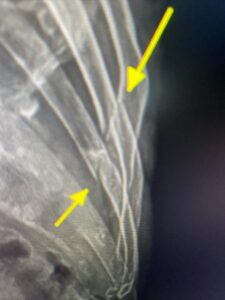

We saw a few broken bones in our office this week as well. You can see in pictures above, the broken ribs on the elderly patient (left) and the broken collar bone on the 6 year old (right). We use a similar protocol to support bone issues such and osteopenia and osteoporosis along with broken bones.